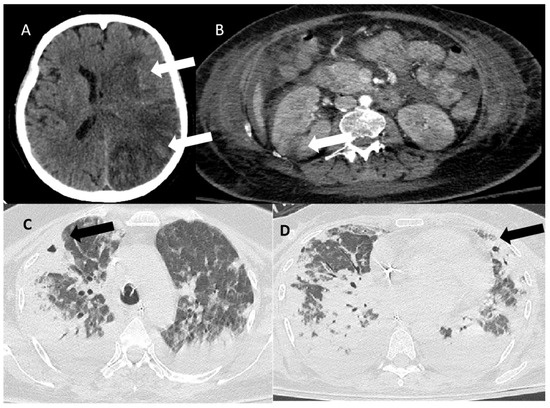

Soon after ICU admission, oxygenation status further worsened, and the patient was finally intubated. To further evaluate the reason for aortic insufficiency and general systolic/diastolic cardiac function, bedside echocardiography was performed, revealing a mass attached to the downstream side of the left coronary cusp of the aortic valve (Figure 1). Severe aortic insufficiency with two eccentric jets were visualized (Figure 1, Videos S1 and S2).

There was also a smaller lesion attached to the posterior leaflet of the mitral valve and a mobile mass in the right ventricle attached to the tricuspid valve (Videos S3 and S4 and Figure 1). As the findings strongly indicated the presence of possible infective endocarditis, gentamycin was added to the patient’s antimicrobial regime (which included meropenem and vancomycin instead of linezolide, trimethoprime-sulphamethoxazole, moxifloxacin, and oseltamivir).

Figure 1. Echocardiographic findings presenting lesions in multiple valves. (A,B) Parasternal long-axis view showing a mass (vegetation) attached to the ventricular surface of the aortic valve (indicated by the white arrow). There is significant aortic regurgitation with two eccentric jets. (C) Parasternal long-axis view showing a mass attached to the atrial surface of mitral valve (white arrow). (D) Modified parasternal short-axis view focusing on the right chambers, showing a thin vegetation attached to the ventricular surface and the subvalvular apparatus of the tricuspid valve (white arrow). There is also vegetation attached to the aortic valve (white arrow).